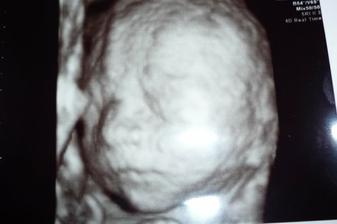

8.2. o 2:55hod sa nam narodil náš chrústik Tomáško, meral 51cm a vážil 3680g,po príchode z pôrodnice vážil 3430g a na poradni v 5 týždnoch meral 59,5cm a vážil 4810g.

Náš vytúžený chrústik Tomáško